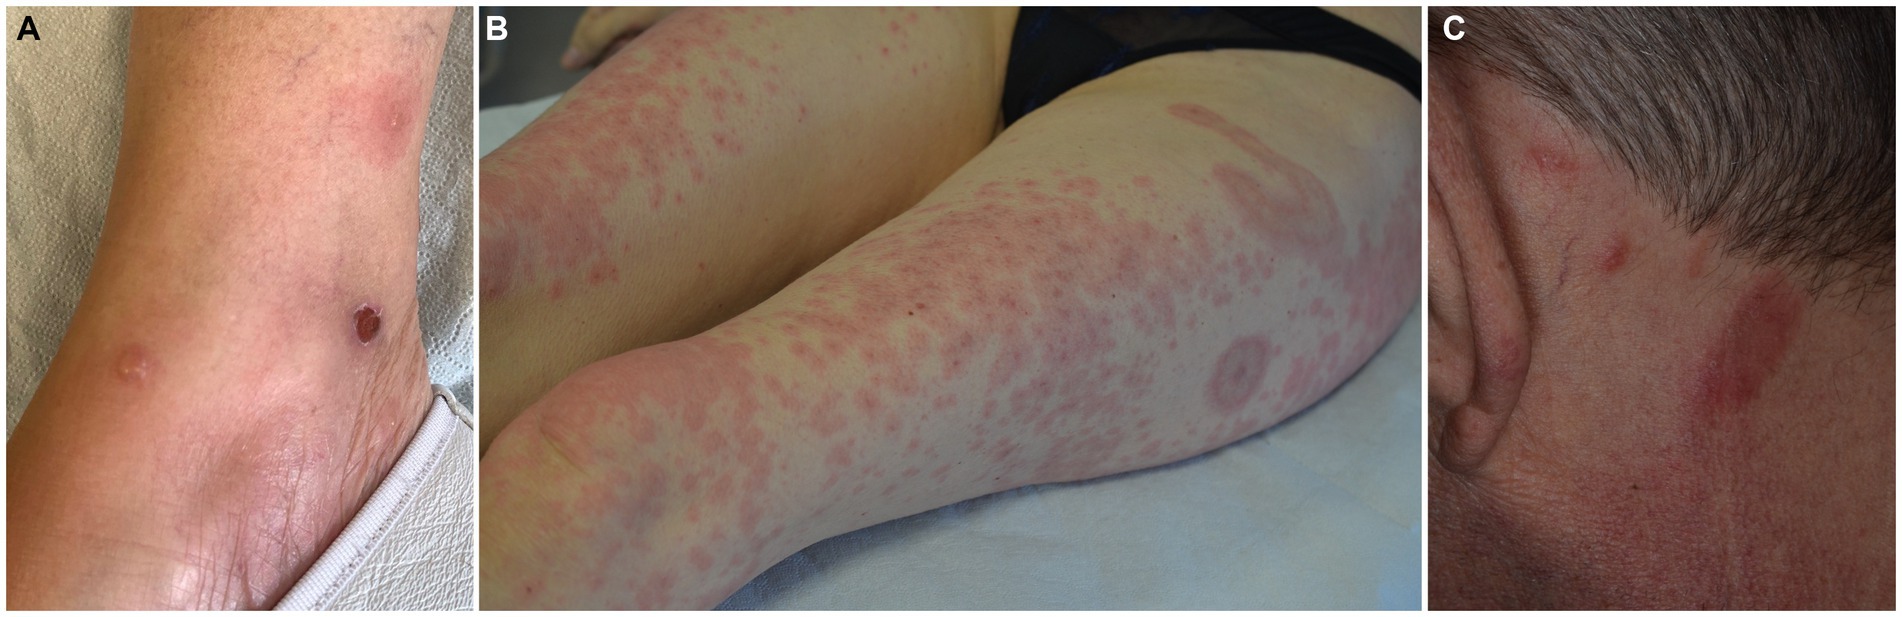

M551 EOSINOPHILIC CELLULITIS: A TREATMENT REFRACTORY CASE - Annals of Allergy, Asthma \u0026 Immunology